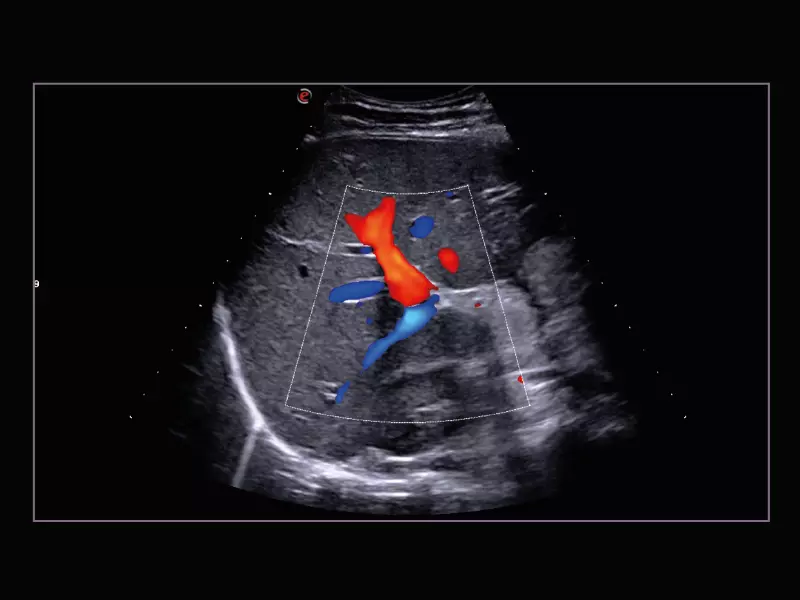

MyLab™C30 - Aorta

MyLab™C30 - Aorta